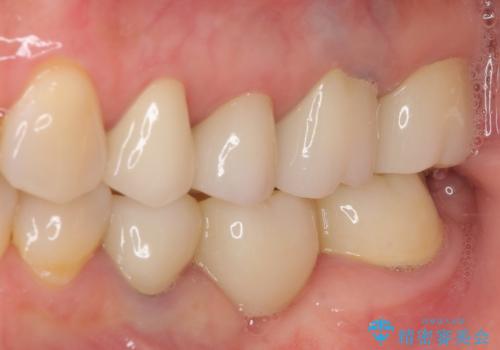

金属を全てセラミックに メタルフリー治療

- 口腔内にある銀歯を全て外したいとのことで来院された患者様です。

土台に含まれている金属も含め、口腔内の金属は全て除去し、抜歯しなければならない歯は抜歯し、オールセラミッククラウンやセラミックインレーにて治療することとしました。

上下奥歯の抜歯を同時期に行わず、下顎の治療を終えてから上顎を抜歯して治療を進めたため、1年ほどの期間を要しました。

口の中を一切気にしなくて良くなり、患者様には大変満足していただきました。